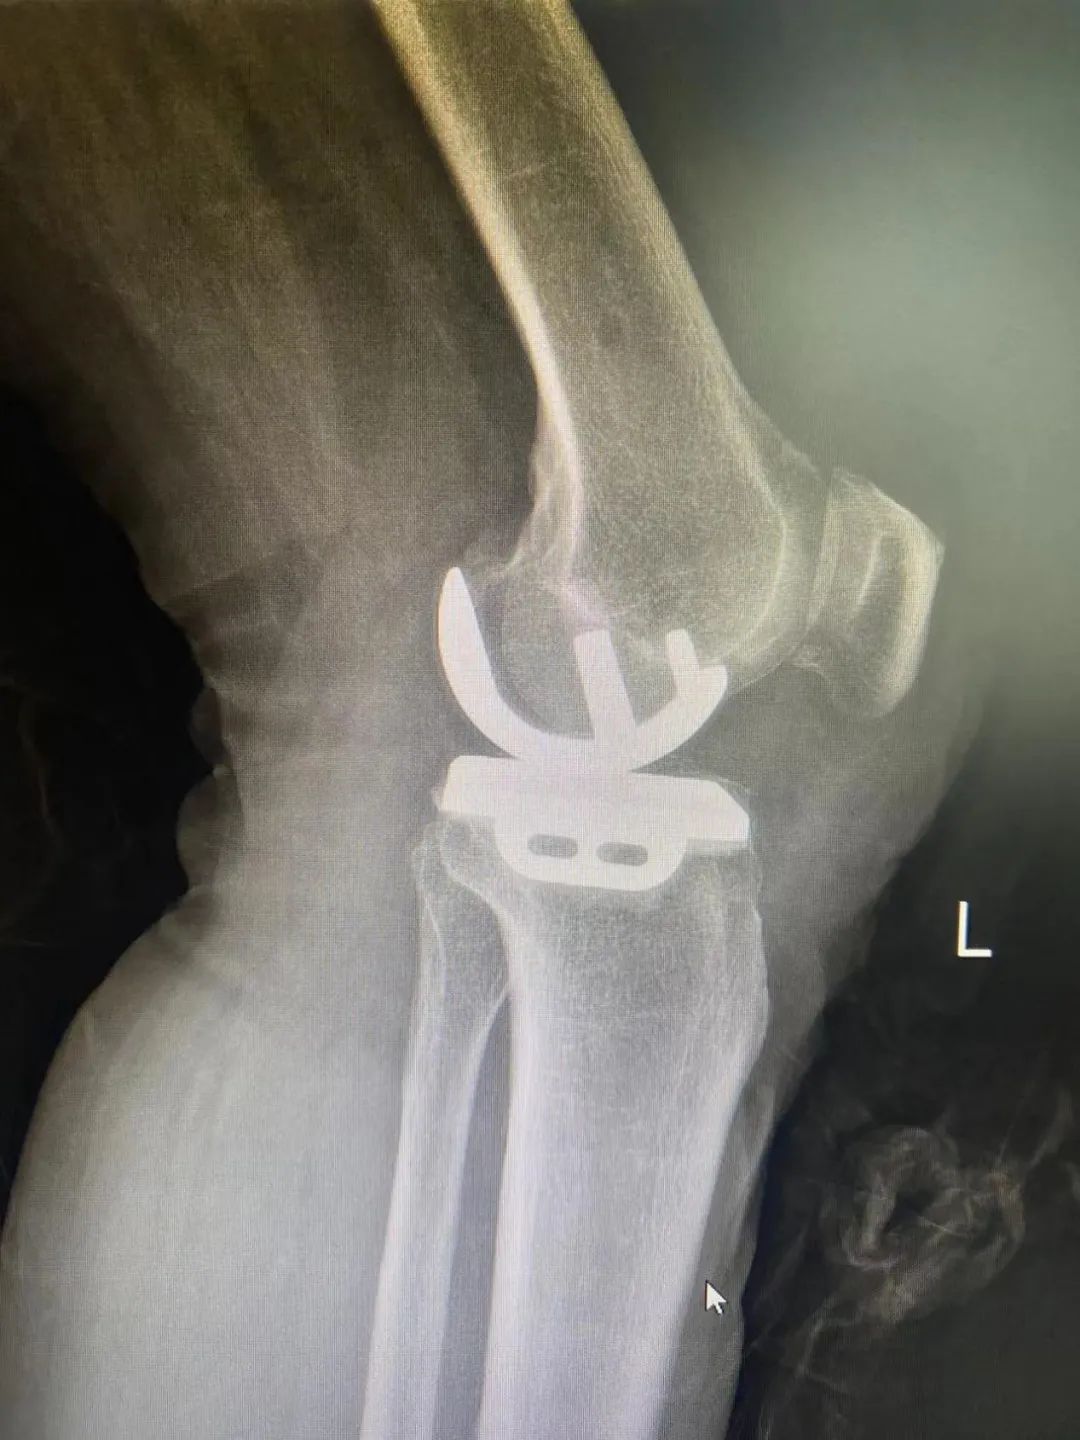

膝关节疼痛背后的真相 术前检查片 老年膝关节疼痛通常被认为是由于骨头磨损所致,但实际情况可能更为复杂。例如,73岁的梁大姐就经历了这种痛苦。她的症状包括走路困难、关节肿胀和持续的疼痛。经过详细的检查和诊断,医生发现梁大姐患有膝关节内侧自发性骨坏死,这是一种不常见的疾病。这种病症涉及到软骨的退变、软骨下骨的水肿以及骨头的坏死,这些因素共同导致了剧烈的疼痛。 单髁置换术——治疗新选择 针对梁大姐的情况,ky骨科一区的许国胜主任提出了三种手术方法:关节镜手术、全膝关节置换术和单髁置换术。考虑到创伤大小、术后恢复速度和功能恢复等因素,最终选择了单髁置换术。这种手术仅更换受坏死影响的内侧间室骨头,同时保留了外侧间室、髌股关节和交叉韧带的正常功能。与传统全膝关节置换相比,单髁置换具有创伤小、疼痛轻、恢复快等优点。 术后效果与快速康复 梁大姐在接受了内侧单髁置换术后,第二天就能下地走路,并在术后第三天出院回家。一个月后复查时,她的左膝关节内侧疼痛症状完全消失,关节活动自如。这一案例证明了单髁置换术的有效性。此外,该手术在国外已有超过30年的历史,在国内外也有超过15年的应用时间,技术成熟且效果稳定可靠。对于早期病变的患者来说,单髁置换术不仅能明显改善生活质量,还能延缓全膝置换的时间。